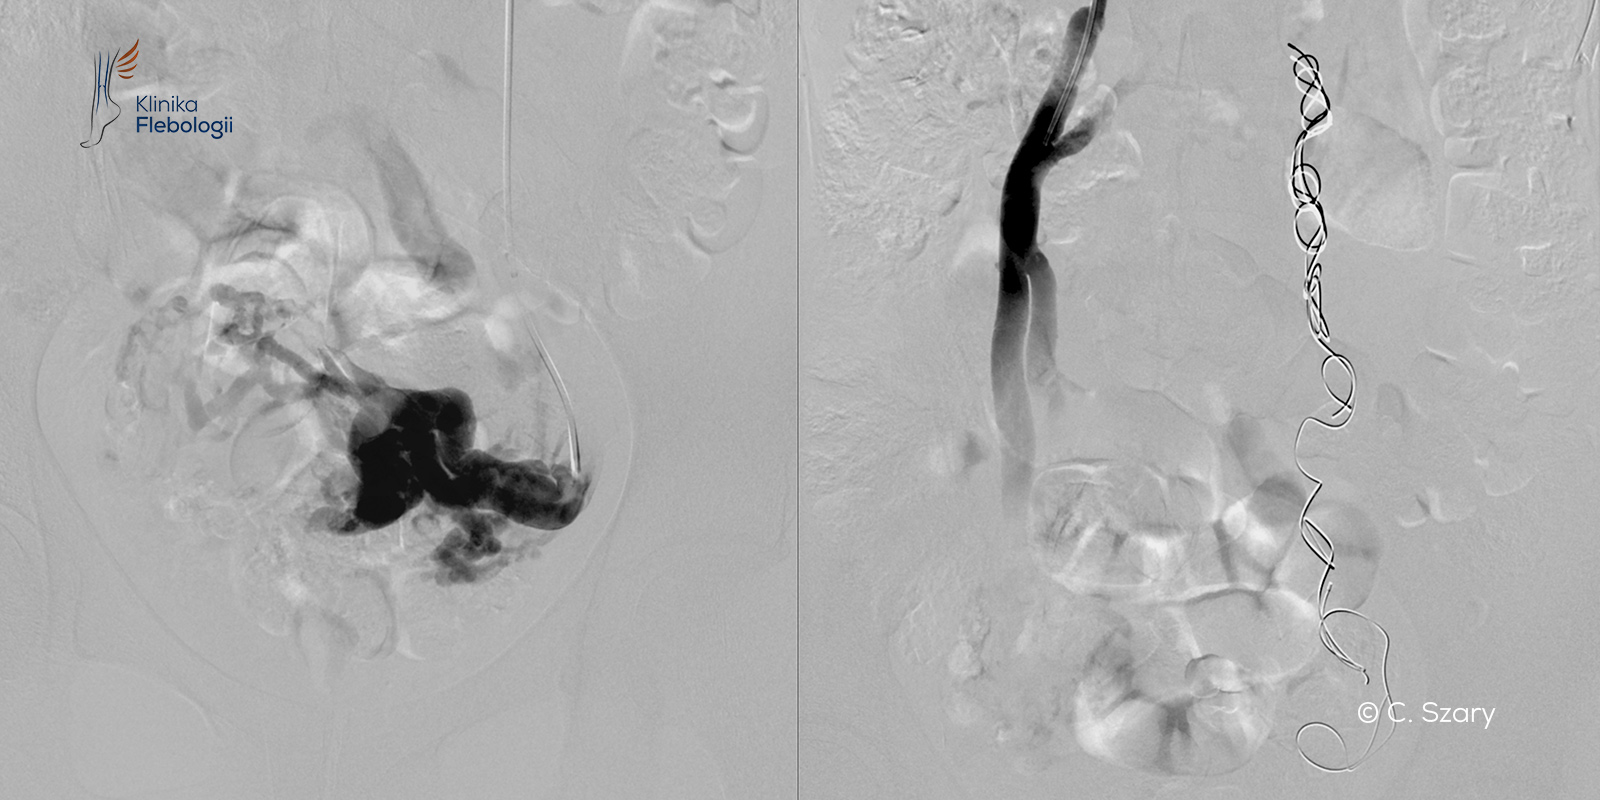

W pracowni hemodynamiki Szpitala Medicover stosujemy zdecydowanie najczęściej zabiegi małoinwazyjne przeprowadzane drogą wewnątrznaczyniową. Każdy zabieg wykonywany jest pod kontrolą sondy USG i cyfrowej aparatury angiograficznej (tworzony jest tzw. venogram).

Procedura embolizacji żylnej przeprowadzana jest w trybie 6-8 godzinnego przyjęcia do szpitala, zwykle bez konieczności stosowania znieczulenia ogólnego, jedynie w płytkiej sedacji. Pacjent jest przytomny i reaguje na polecenia lekarzy wydawane w czasie zabiegu.

czytaj więcejW dobie cyfryzacji sprzętu angiograficznego (bazującego na promieniach rtg), poprawie jakości obrazowania oraz wzrostu bezpieczeństwa środków kontrastowych flebografia diagnostyczna wykonywana na sali przeznaczonej zabiegów wewnątrznaczyniowych, stała się wyjątkowo precyzyjnym narzędziem w ocenie wielu stanów klinicznych związanych z chorobami układu żylnego.

czytaj więcejGłówne wskazania to: objawowa niewydolność żylna miednicy (tzw. zespół przekrwienia biernego miednicy); atypowe żylaki kończyn dolnych wynikające z niewydolności żylnej miednicy...